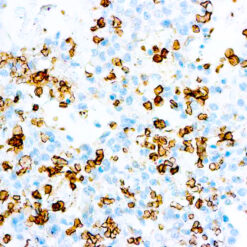

Calponin-1

Multiple isoelectric variants of calponin have been identified but only two molecular weight isoforms exist (34kDa and 29kDa). Expression of the 29kDa form, I-calponin, is primarily restricted to muscle of the urogenital tract, whereas the higher molecular weight variant has been demonstrated in vascular and visceral smooth muscle. Calponin is a calmodulin, F-actin and tropomyosin binding protein, which is thought to be involved in the regulation of smooth muscle contraction. Calponin expression is restricted to smooth muscle cells and has been shown to be a marker of the differentiated (contractile) phenotype of developing smooth muscle.

| Cellular Localization | Cytoplasmic |